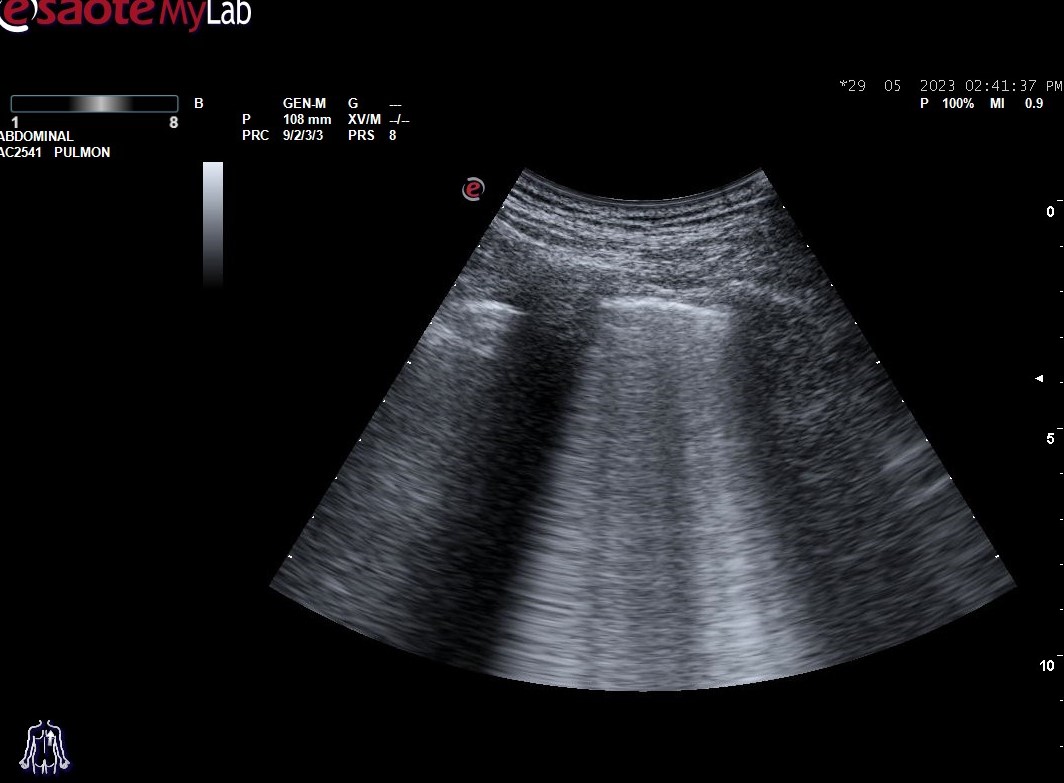

Hallazgos ecográficos: derrame pleural bilateral y abundantes líneas B (más de 3 por espacio intercostal) en ambos 1/3 medios inferiores bilaterales (adjuntamos imágenes).

En la ecografía pulmonar observamos unos patrones ecográficos (normal, deslizamiento pleural, líneas A, líneas B, derrame pleural y consolidación pulmonar). Realizando una serie de preguntas dicotómicas sobre estos patrones ecográficos se establece un algoritmo (protocolo BLUE) que permite establecer con alta sensibilidad y especificidad la causa de la disnea mediante un árbol de decisión.

Aplicando dicho protocolo establecemos un diagnóstico ecográfico de presunción de Edema Agudo de Pulmón/Insuficiencia cardíaca.